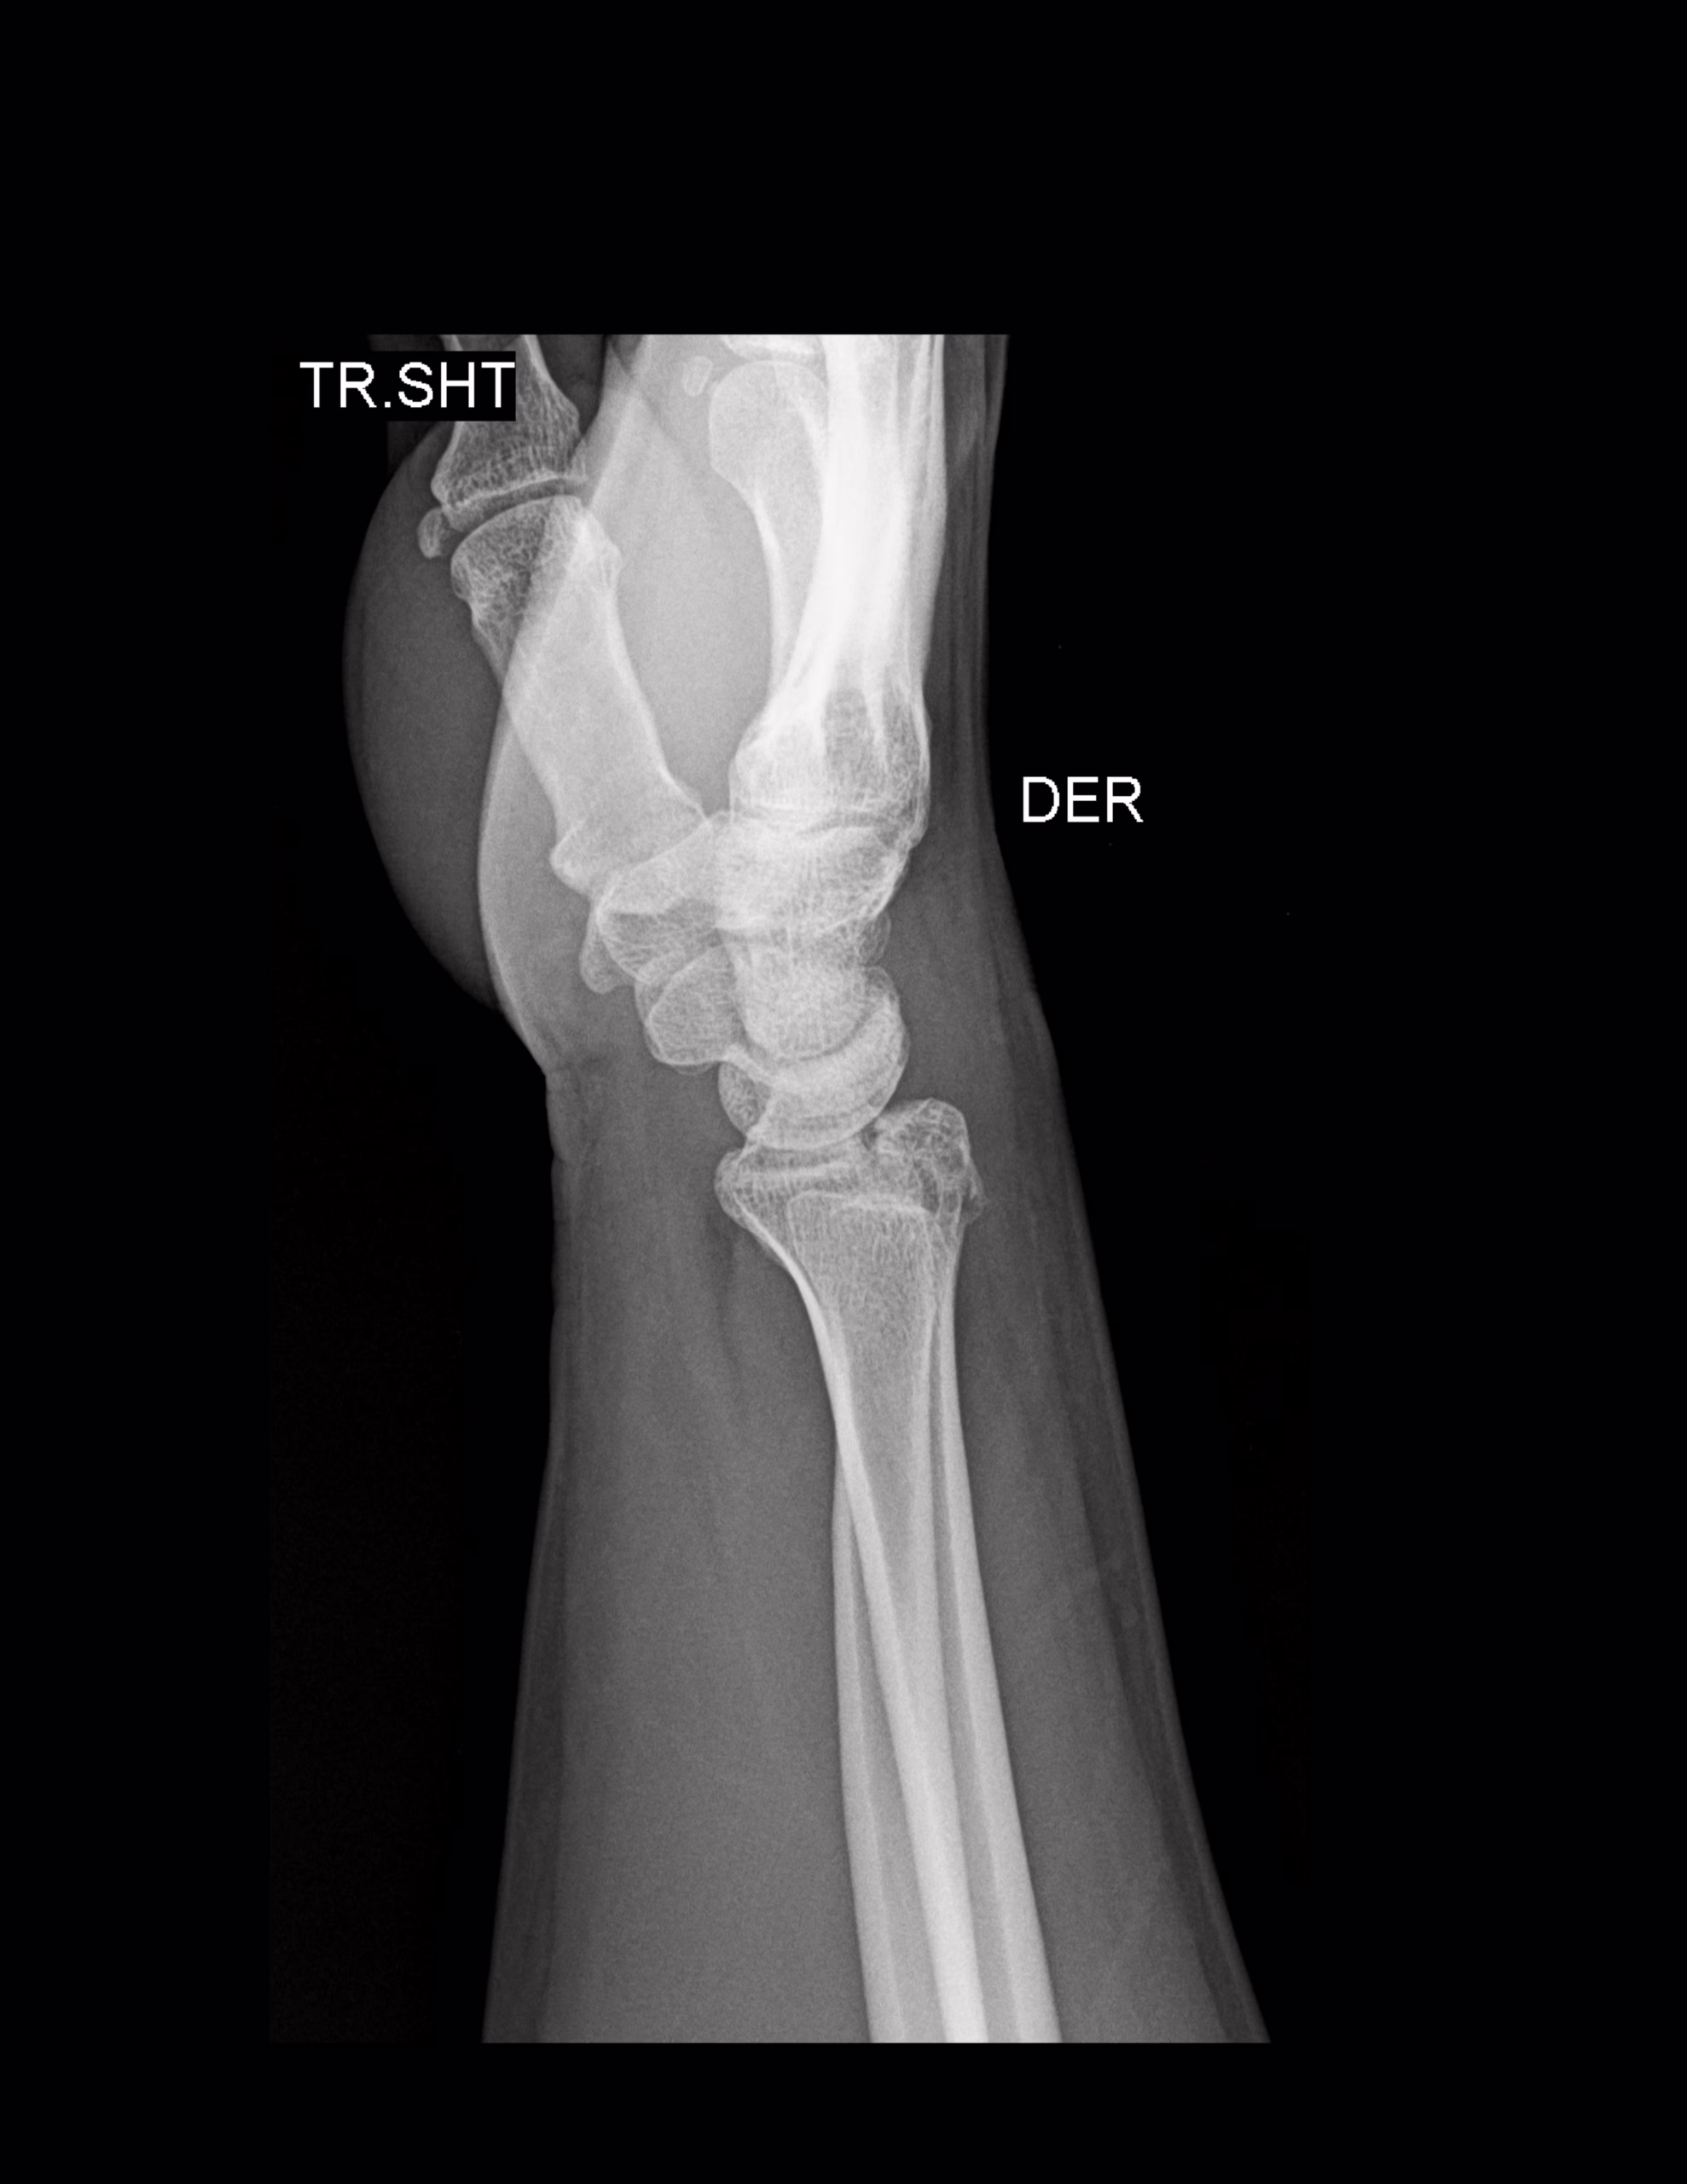

RADIOGRAFIAS AP Y LATERAL DE MUÑECA

Hallazgos:

-En lo observado de radio y cubito, a nivel de porción dorsal del radio se observa trayecto oblicuo intraarticular sin desplazamientos. Resto de lo observado de radio y cubito, sin alteraciones. .

-Huesos del carpo, metacarpos y falanges, sin evidencia de lesiones blásticas, líticas o perdidas de la contigüidad.

-Articulaciones con adecuada amplitud.

-Tejidos blandos, con aumento la densidad y grosor a nivel dorsal de muñeca. Resto con adecuada densidad y grosor.

-Longitud radial de 16 mm.

-Angulación radial de 34°.

-Longitud de apófisis estiloides del cúbito de 5.5 mm.

-Angulo escafolunado de 43.8°

-ángulo grandelunado de 4.3°

-ángulo volar de 4.1°

OPINIÓN RADIOLÓGICA:

EN EL PRESENTE ESTUDIO RADIOGRÁFICO, EXISTE FRACTURAS DE LA PORCIÓN DORSAL DEL RADIO (FRACTURA DORSAL DE BARTON) CON EDEMA ASOCIADO.

LEER DESCRIPCIÓN Y OTORGAR VALOR DIAGNÓSTICO.

CORRELACIONAR CON DATOS E HISTORIA CLINICA DEL PACIENTE.